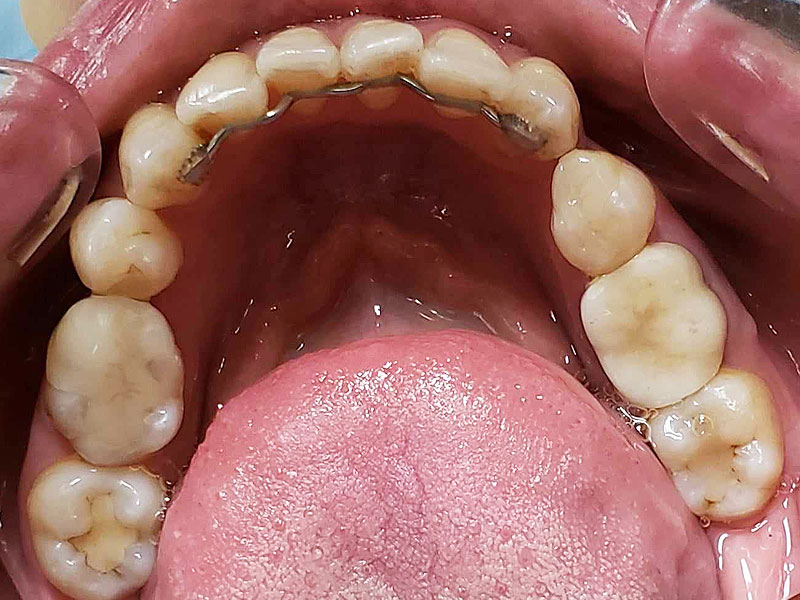

術前

• 初診:2006年、2014年―矯正治療を含めた一口腔単位の治療開始、治療当時、30代女性、非喫煙者

• 主訴:できれば歯並びを良くし歯を白くしたい。

• 治療方針:親知らず3本抜歯、上下小臼歯4本抜歯、矯正用インプラント使用のワイヤー矯正、修復処置、保定(上マウスピース、下ワイヤー)、メンテナンス